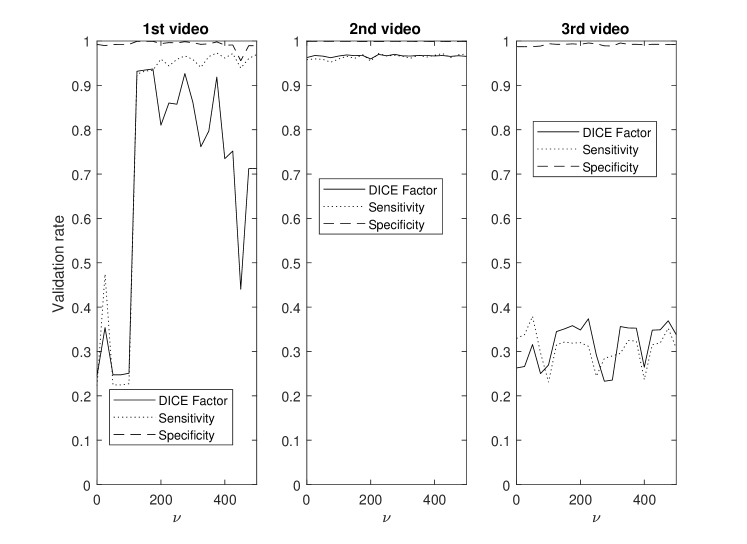

This section demonstrates the robustness of the algorithm for each parameter along with the relative importance of each parameter on the overall performance. This enables the identification and potential removal of weak features from the energy function in order to improve computational efficiency. For this study, the average DICE factor, sensitivity, and specificity of three different clips versus the initial parameters , , , , and are shown in Figs. 5-10. In the all of these figures, one can easily see that the specificity is always very close to one indicating a relatively small rate of .

The three test videos suggest setting to one supports optimal segmentation as shown in Fig. 5. Large values of result in excessive contour shrinking while small values reduce contour smoothness.

The parameter demonstrates optimal performance near zero as per Fig. 6. This strongly suggests that the continuity energy term is a weak feature and hence, can be removed from the energy function.

In Fig. 7, all three videos provide their best performance at a between 0.04 and 0.08, hence, is set at 0.06. In two of the three test videos, the edge energy does not significantly improve the segmentation performance as the curves appear flat around likely resulting from indistinct edges and consequently, providing limited information to improve segmentation results.

Fig. 8 highlights that different videos demonstrate considerable variance in sensitivities versus . Sensitivity was relatively stable for ranging between 0.4 and 0.9, hence was set to 0.8.

For the parameter , the best performance was established between 125 - 175 as shown in Fig. 9. Hence, equal to 150 seems to be an appropriate selection.

Finally Fig. 10 shows that the best performance is obtained when is between 0.0009 and 0.0015 resulting in as an appropriate selection.